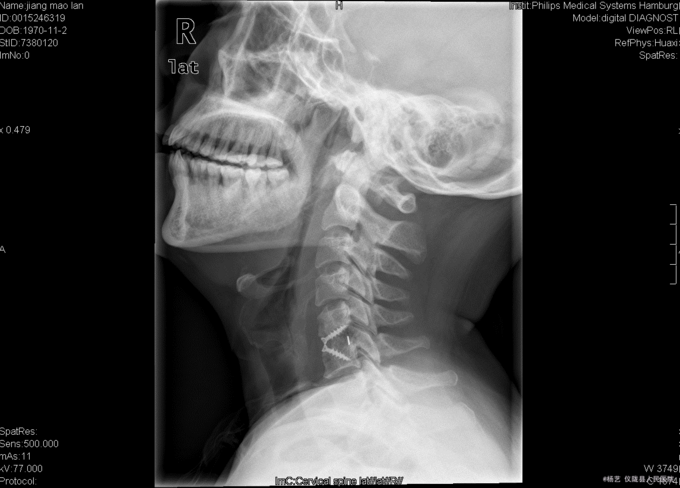

患者蒋茂兰,女,45岁0月,因“头晕伴视物旋转10+月,加重1+月。”入院 10+月前患者无明显诱因出现头晕、头昏;视物旋转,偶伴有呕吐,呕吐为胃内容物;间断发作,发作时持续时间不等,休息后明显缓解。无活动障碍;无肢体麻木、乏力;无行走不稳;无发热、头痛等,1+月前患者上述症状加重,患者于当地医院就诊,治疗未见明显好转。颈椎MRI示:颈5/6椎间盘突出。现患者为求进一步诊治就诊于我院,门诊以“C5/6椎间盘突出症伴脊髓神经不全损害”收入我科。

查体:T:36.9oC,P:78次/分,R:19次/分,BP:109/72mmHg。神志清楚,无病容,皮肤巩膜无黄染,全身浅表淋巴结未见肿大。。颈静脉正常。心界正常,心律齐,各瓣膜区未闻及杂音。胸廓未见异常,双肺叩诊呈清音,双肺呼吸音清,未闻及干湿啰音及胸膜摩擦音。腹部外形正常,全腹柔软,无压痛及反跳痛,腹部未触及包块,肝脏肋下未触及,脾脏肋下未触及,双肾未触及。双下肢无水肿。 专科查体:视:脊柱外观无畸形,活动无异常,无皮肤破溃及窦道形成。触:椎体棘上、椎旁肌无压痛、叩痛,四肢感觉无明显减退,远端血运未见异常。动量:颈部屈伸、左右侧偏活动无明显受限,双上肢耸肩、屈伸肘关节、屈伸腕肌力5级,双手握力5级,双下肢伸髋、屈髋、外展、内收、伸膝、屈膝肌力5级,双足趾背伸肌力5级。双侧肱二、三头肌肌腱反射、膝腱反射、跟腱反射正常引出。双侧Hoffmann氏征阳性,Babinski征阴性,踝阵挛阴性,髌阵挛阴性。 辅助检查:外院MRI示:颈椎退行性变,颈5/6椎间盘突出。垂体区:空泡蝶鞍?

综上初步诊断:1、颈5-6椎间盘突出症伴脊髓神经不全损害;2、白癜风 经前路颈5/6椎间盘切除、椎管及椎间孔减压、椎间融合器植骨融合内固定术。 手术发现:  颈5/6椎间隙变窄,椎间盘髓核干涩,无光泽。颈5/6椎间隙后份少量骨赘生成,椎间盘向后方突出,压迫硬脊膜。术中夹出数块突入椎管内的椎间盘髓核组织及增生骨赘。充分减压后,可见硬脊膜恢复膨隆,双侧神经根松弛,术中未见脑脊液漏。